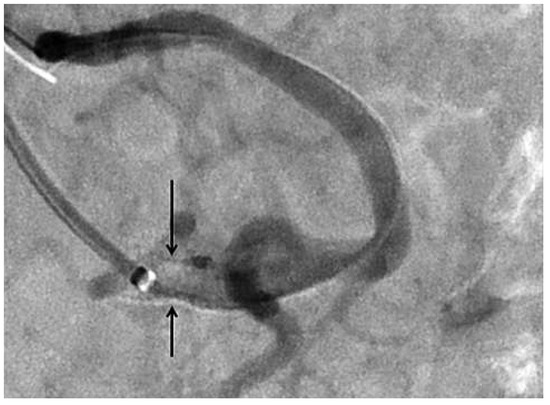

Using a left brachial approach, the coeliac trunk was cannulated with a multipurpose 5F catheter, 125 cm long, inserted over a 6F 90-cm-long sheath. 250 mg aspirin IV and 6000 units unfractionated heparin IV were administered. Angiography revealed a subtotal lesion of the coeliac trunk (Figure 2) and of the superior mesenteric artery (Figure 3). The coeliac lesion was passed with a 0.014” BMW wire (Abbott) and then exchanged over a Minnie Microcatheter (Vascular Solutions) for an Iron Man 0.014” 300-cm-long stiff wire (Abbott). Balloon predilatation was performed with a 4.0 × 20 mm Avion balloon (Invatec) and followed by placement of a 7 × 15 mm Hyppocampus at 14 atmospheres (Medtronic) (final diameter 7.6 mm) with a good final angiographic result (Figure 4). Since reperfusion of one vessel is usually sufficient to reverse mesenteric ischaemia we refrained from approaching the superior mesenteric artery. 600 mg clopidogrel PO were administered at the end of the procedure.

Figure 2.

Digital subtraction angiography of the abdominal aorta, performed via left brachial approach, showing a subtotal lesion at the origin of the coeliac trunk (arrow).

Figure 3.

Digital subtraction angiography of the abdominal aorta showing severe stenosis of the origin of the mesenteric superior artery (arrow).